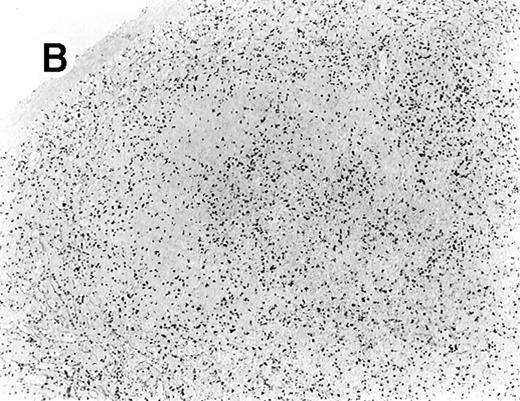

All cases showed essentially similar histologic findings in the liver and spleen. The splenic white pulp was inconspicuous to markedly depleted, whereas the sinusoids showed a prominent lymphoid infiltration (Figure 1A). There was striking hemophagocytosis within the splenic sinusoids (Figure 1B). The infiltrating lymphocytes were small and lacked significant cytologic atypia (Figure 1B). Immunoblasts and plasma cells were not prominent. The liver had prominent portal as well as sinusoidal infiltrates of small lymphocytes morphologically identical to those noted in the spleen (Figure 2). There was intracellular and intracanalicular cholestasis, steatosis, and focal necrosis. Hemophagocytosis was present within the sinusoids. In case 5, the spleen showed extensive areas of necrosis mainly in the perifollicular and periarteriolar lymphoid sheaths of the white pulp with the presence of immunoblasts reminiscent of IM.

Histologic findings in spleen.

(A) Section of spleen from case 2 shows depletion of white pulp and prominent sinusoidal small lymphoid infiltrates (hematoxylin and eosin, × 200). (B) The lymphocytes lack significant cytologic atypia. There is marked hemophagocytosis (hematoxylin and eosin, × 600).